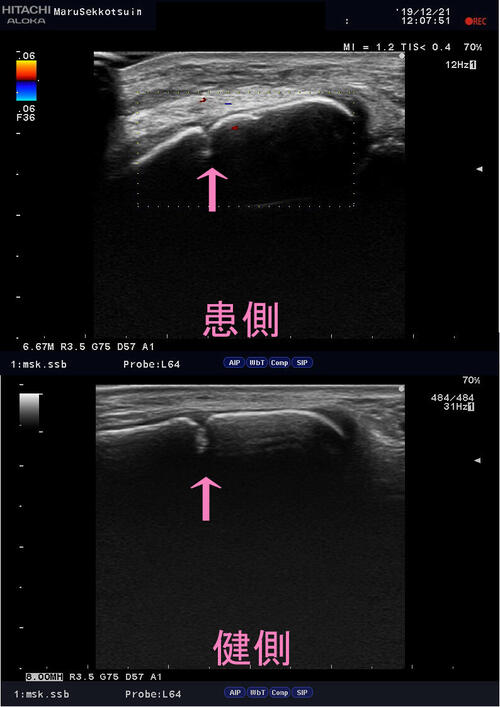

いつも通りよ~く問診、視診、触診後、確認のためエコー検査。

結果「腓骨遠位端部 骨端線離解」の疑い。

骨端線echo.jpg